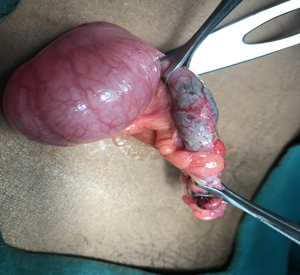

The official name of the appendix is vermiform appendix, which means "worm-like appendage". It is a small, pouch-like sac of tissue that is located in the first part of the colon (cecum) in the lower- right abdomen. Appendix plays a role in immune function by its lymphatic tissue. It usually harbors bacteria.

At Remedy Hospital we offer surgery for all conditions of appendix like appendicitis, appendicular malignancy, and mucocele of appendix. We offer surgery by latest technique (Laparoscopic Appendectomy) as well as time tasted conventional technique (Open Appendectomy).